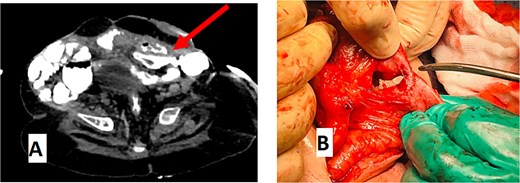

An abdominal CT scan with oral contrast revealed two ECFs: the first connected to the small bowel (Fig. 6, green arrow, corresponding to fistula number 1 in Fig. 5), and the second connected to the proximal sigmoid colon (Fig. 6, blue arrow, corresponding to fistula number 2 in Fig. 5). Furthermore, an enteroenteric fistula between the ileum and rectosigmoidal junction was noted (Fig. 7, red arrow).

(A) CT abdomen with oral contrast showing enteroenteric fistula. The red arrow indicates a fistula between the ileum and the rectosigmoid junction. (B) Gross appearance of the enteroenteric fistula.